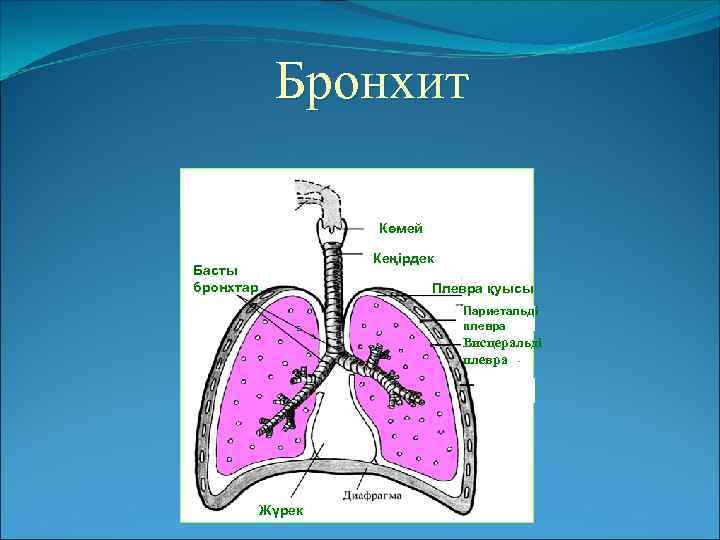

Бронхтардың құрылысы Басты бронхтар Бөліктік бронхтар Сегменттік бронхтардың тармақталуы Бөлшектері Бөлшектік бронхтар Терминалды бронхиолалар Ацинустар